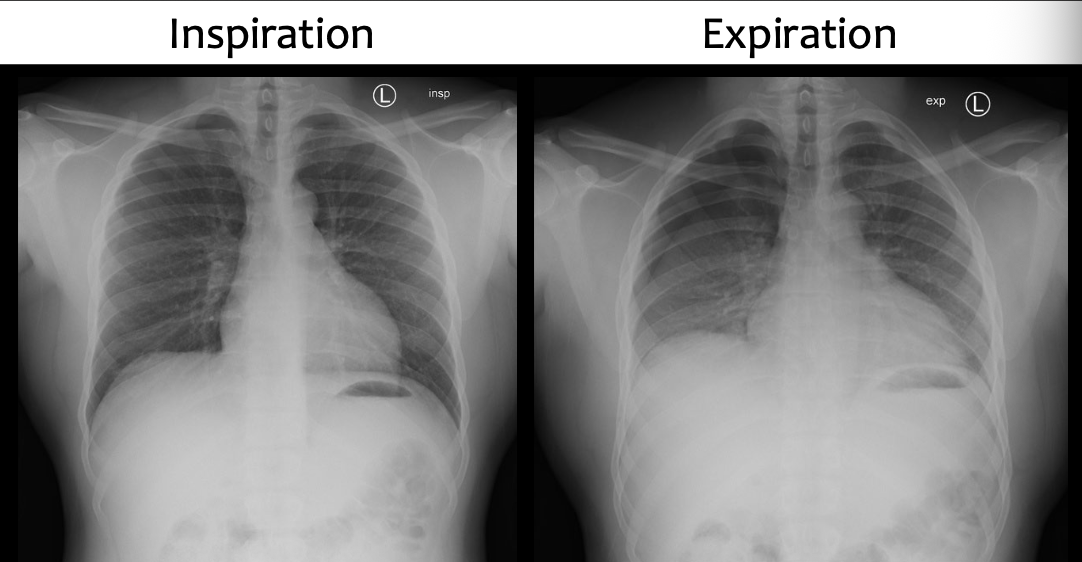

Why would an expiration CXR be performed?

To increase the conspicuity of small pneumothoraces. It increases the attenuation of normal lung, thereby increasing the contrast between lung and pneumothorax.